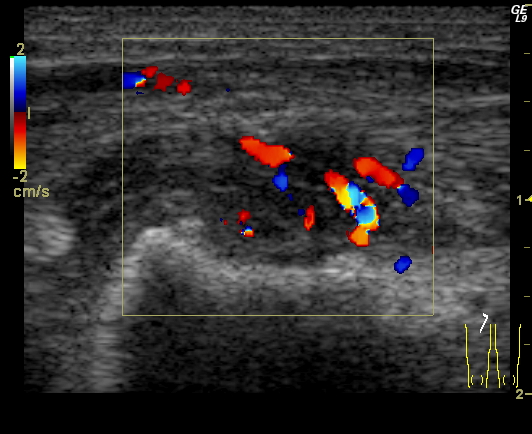

Malrotation-volvulus. During the normal development of the intestinal tract, the intestinal loops make three 90 degree clock-wise rotations around the mesenteric superior artery (MSA.) If this rotation only partially occurs during the embryonic development the intestines remain in a non-rotational or malrotational position, the mesenteric root will be shorter and the cecum will be weakly attached. This anatomic positioning can be symptom free throughout a lifetime, but it predisposes for volvulus. Volvulus can occur at any age, but it is most frequent in the first months of life, when it abruptly occurs with acute bilious vomiting. In this state the intestines around the mesenteric root twist, end up in a complete obstruction that can lead to a rapid death of the intestines. Ultrasonography can depict the mesenteric superior vein (MSV) coiled up around the MSA, so called “whirlpool”-sign.

14. “Whirlpool” sign The mesentery and the superior mesenteric vein, as it coils around the superior mesenteric artery. Volvulus. US exam.

Image